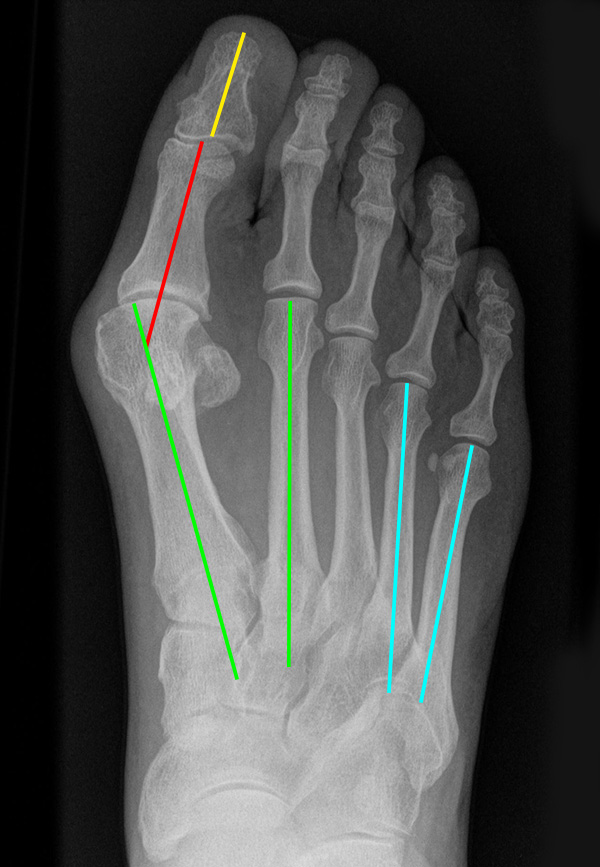

Vorfußbreite

Eine Verbreiterung des Vorfußes wird als Spreizfuß bezeichnet. Ursächlich ist meist eine Deviation des ersten Metatarsale nach medial und/oder eine Abweichung des fünften Metatarsale nach lateral. Die Abweichung kann im Röntgenbild quantifiziert werden. Der Winkel zwischen Os metatarsale I und II wird als pathologisch zu bezeichnet, wenn er in der belasteten dorsoplantaren Röntgenaufnahme 9° überscheitet. Der Intermetatarsalwinkel IV/V wird ab einem Wert von mehr als 8° als erhöht.

Abbildung 15: Schwere Spreizfußdeformität (M. Walther).

Abbildung 16: Belastetes dorsoplantares Röntgenbild des Fußes. Zur Beurteilung des Spreizfußes wird der Intermetatarsalwinkel I/II (grüne Linien - Norm < 9 Grad) und der Intermetatarsalwinkel IV/V (blaue Linien - Norm < 8°) bestimmt. Die Abweichung der Großzehe ist durch den Hallux valgus Winkel definiert (grüne/rote Linie), eine Fehlstellung innerhalb der Großzehe durch den Interphalangealwinkel (rote/gelbe Linie) (M. Walther).

Zum Lesen der Bildbeschreibung und zur Vollansicht bitte die Bilder anklicken.